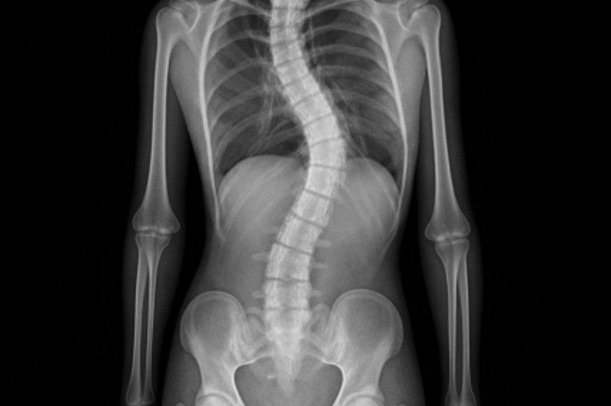

側弯症とは、背骨が左右に弯曲している状態を指すと紹介されています。本来、背骨は正面から見るとまっすぐに近いラインを保つと言われていますが、側弯症では横方向へのカーブが見られると解説されています。成長期に見つかることが多い一方で、大人になってから姿勢の影響で機能的なゆがみが出るケースもあるとされています。引用元:https://fujisawaseitai.com/case-blog/scoliosis-low-back-pain-relationship/

背骨が弯曲すると、体の重心バランスが左右で変わりやすいと言われています。その結果、片側の筋肉に負担が集中することがあると紹介されています。見た目のゆがみだけでなく、筋肉の緊張や可動域の差が生じる点が特徴だと解説されています。引用元:https://fujisawaseitai.com/case-blog/scoliosis-low-back-pain-relationship/